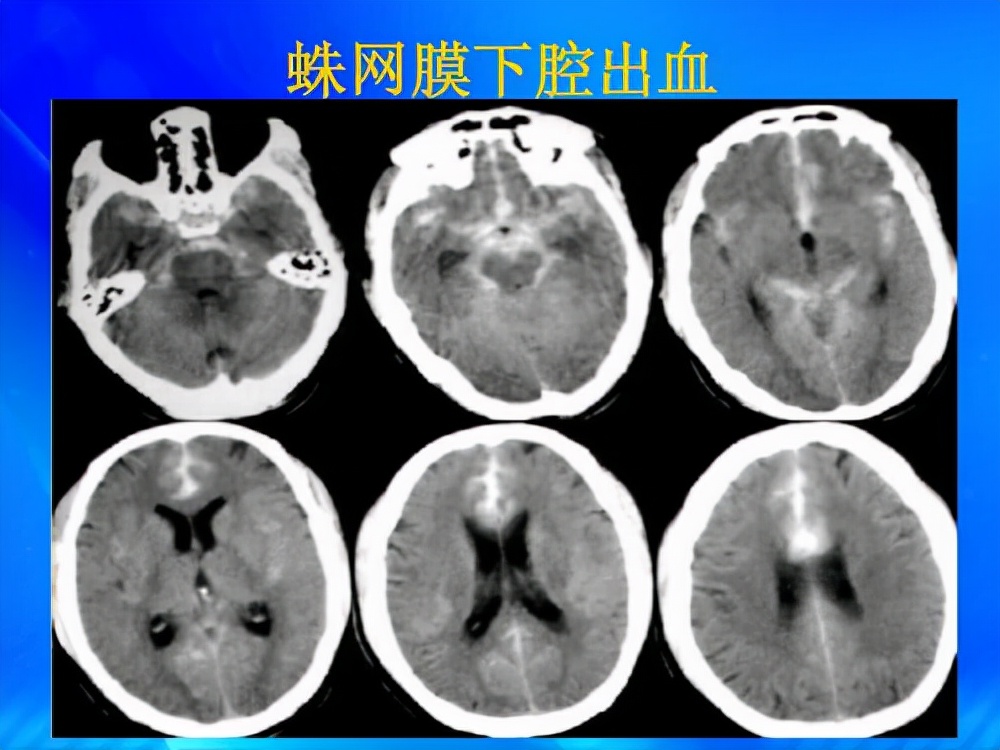

第二名 裂头之痛——蛛网膜下腔出血

人的大脑表面覆盖有三层膜,从内到外分别是软脑膜,蛛网膜以及硬脑膜,而软脑膜与蛛网膜之间的腔隙,就是我们所说的蛛网膜下腔,当脑血管破裂时,血液就会流入我们脑中的这个地方,紧接着就会出现以下4种疼痛:

一,简单头痛。这种情况一般症状较轻,同时还会伴有嗜睡和恶心呕吐。

二,脑膜刺激。这个时期患者会明显感觉到自己的颈部和背部变得僵硬,同时还夹杂着呼吸困难以及丧失意识的情况。

三,爆炸式头痛。到了这个阶段,剧烈的疼痛下,人们会觉得自己的大脑已经裂开,甚至有很多人直言,这是有生以来头最痛的时刻,尤其是针对年轻人来说,至于老人反而不太明显,因为他们会直接痛到昏迷。

四,身体麻木。这个疾病的后期患者会出现意识丧失情况,与此同时还畏光怕冷,身体不断冒冷汗,眼睑下垂,随时有死亡风险,因此如果有头痛情况,还是劝大家尽早去看。